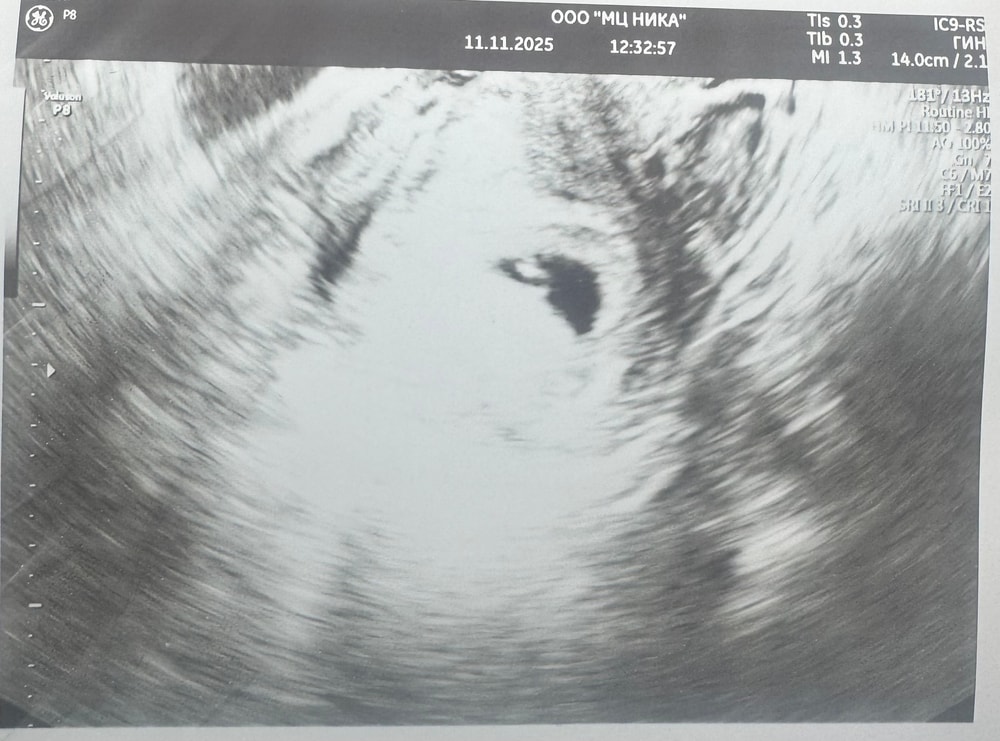

Соня в Благополучная беременность месяц Метод Рамзи Затрудняюсь с категорией Девочки, кто разбирается в методе Рамзи?Узи вагинальное, срок 6 недель и 2 дн Посмотрите еще 20 записей на эту тему Отменить Ответить Ева По методу - девочка:) 11.11.2025 Ответить Ева Ева, 11.11.2025 Ответить Mari Ева, а можете мне тоже посмотреть, пожалуйста 🙏🏻😅 1 узи 6 недель 2 узи 8 недель 11.11.2025 Ответить Ева Mari, у вас девочка по методу, выше скинула референс:) у меня совпало 12.11.2025 Ответить Mari Ева, спасибо большое! Очень надеюсь, что так и есть 😂🙏🏻 12.11.2025 Ответить Соня 11.11.2025 Ответить Шейка на 1 скрининге Зрение у новорожденного Чаты Беременных Выберите чат: Январята-2026 Февралята-2026 Мартята-2026 Апрелята-2026 Майчата-2026 Июнята-2026 Июлята-2026 Августята-2026